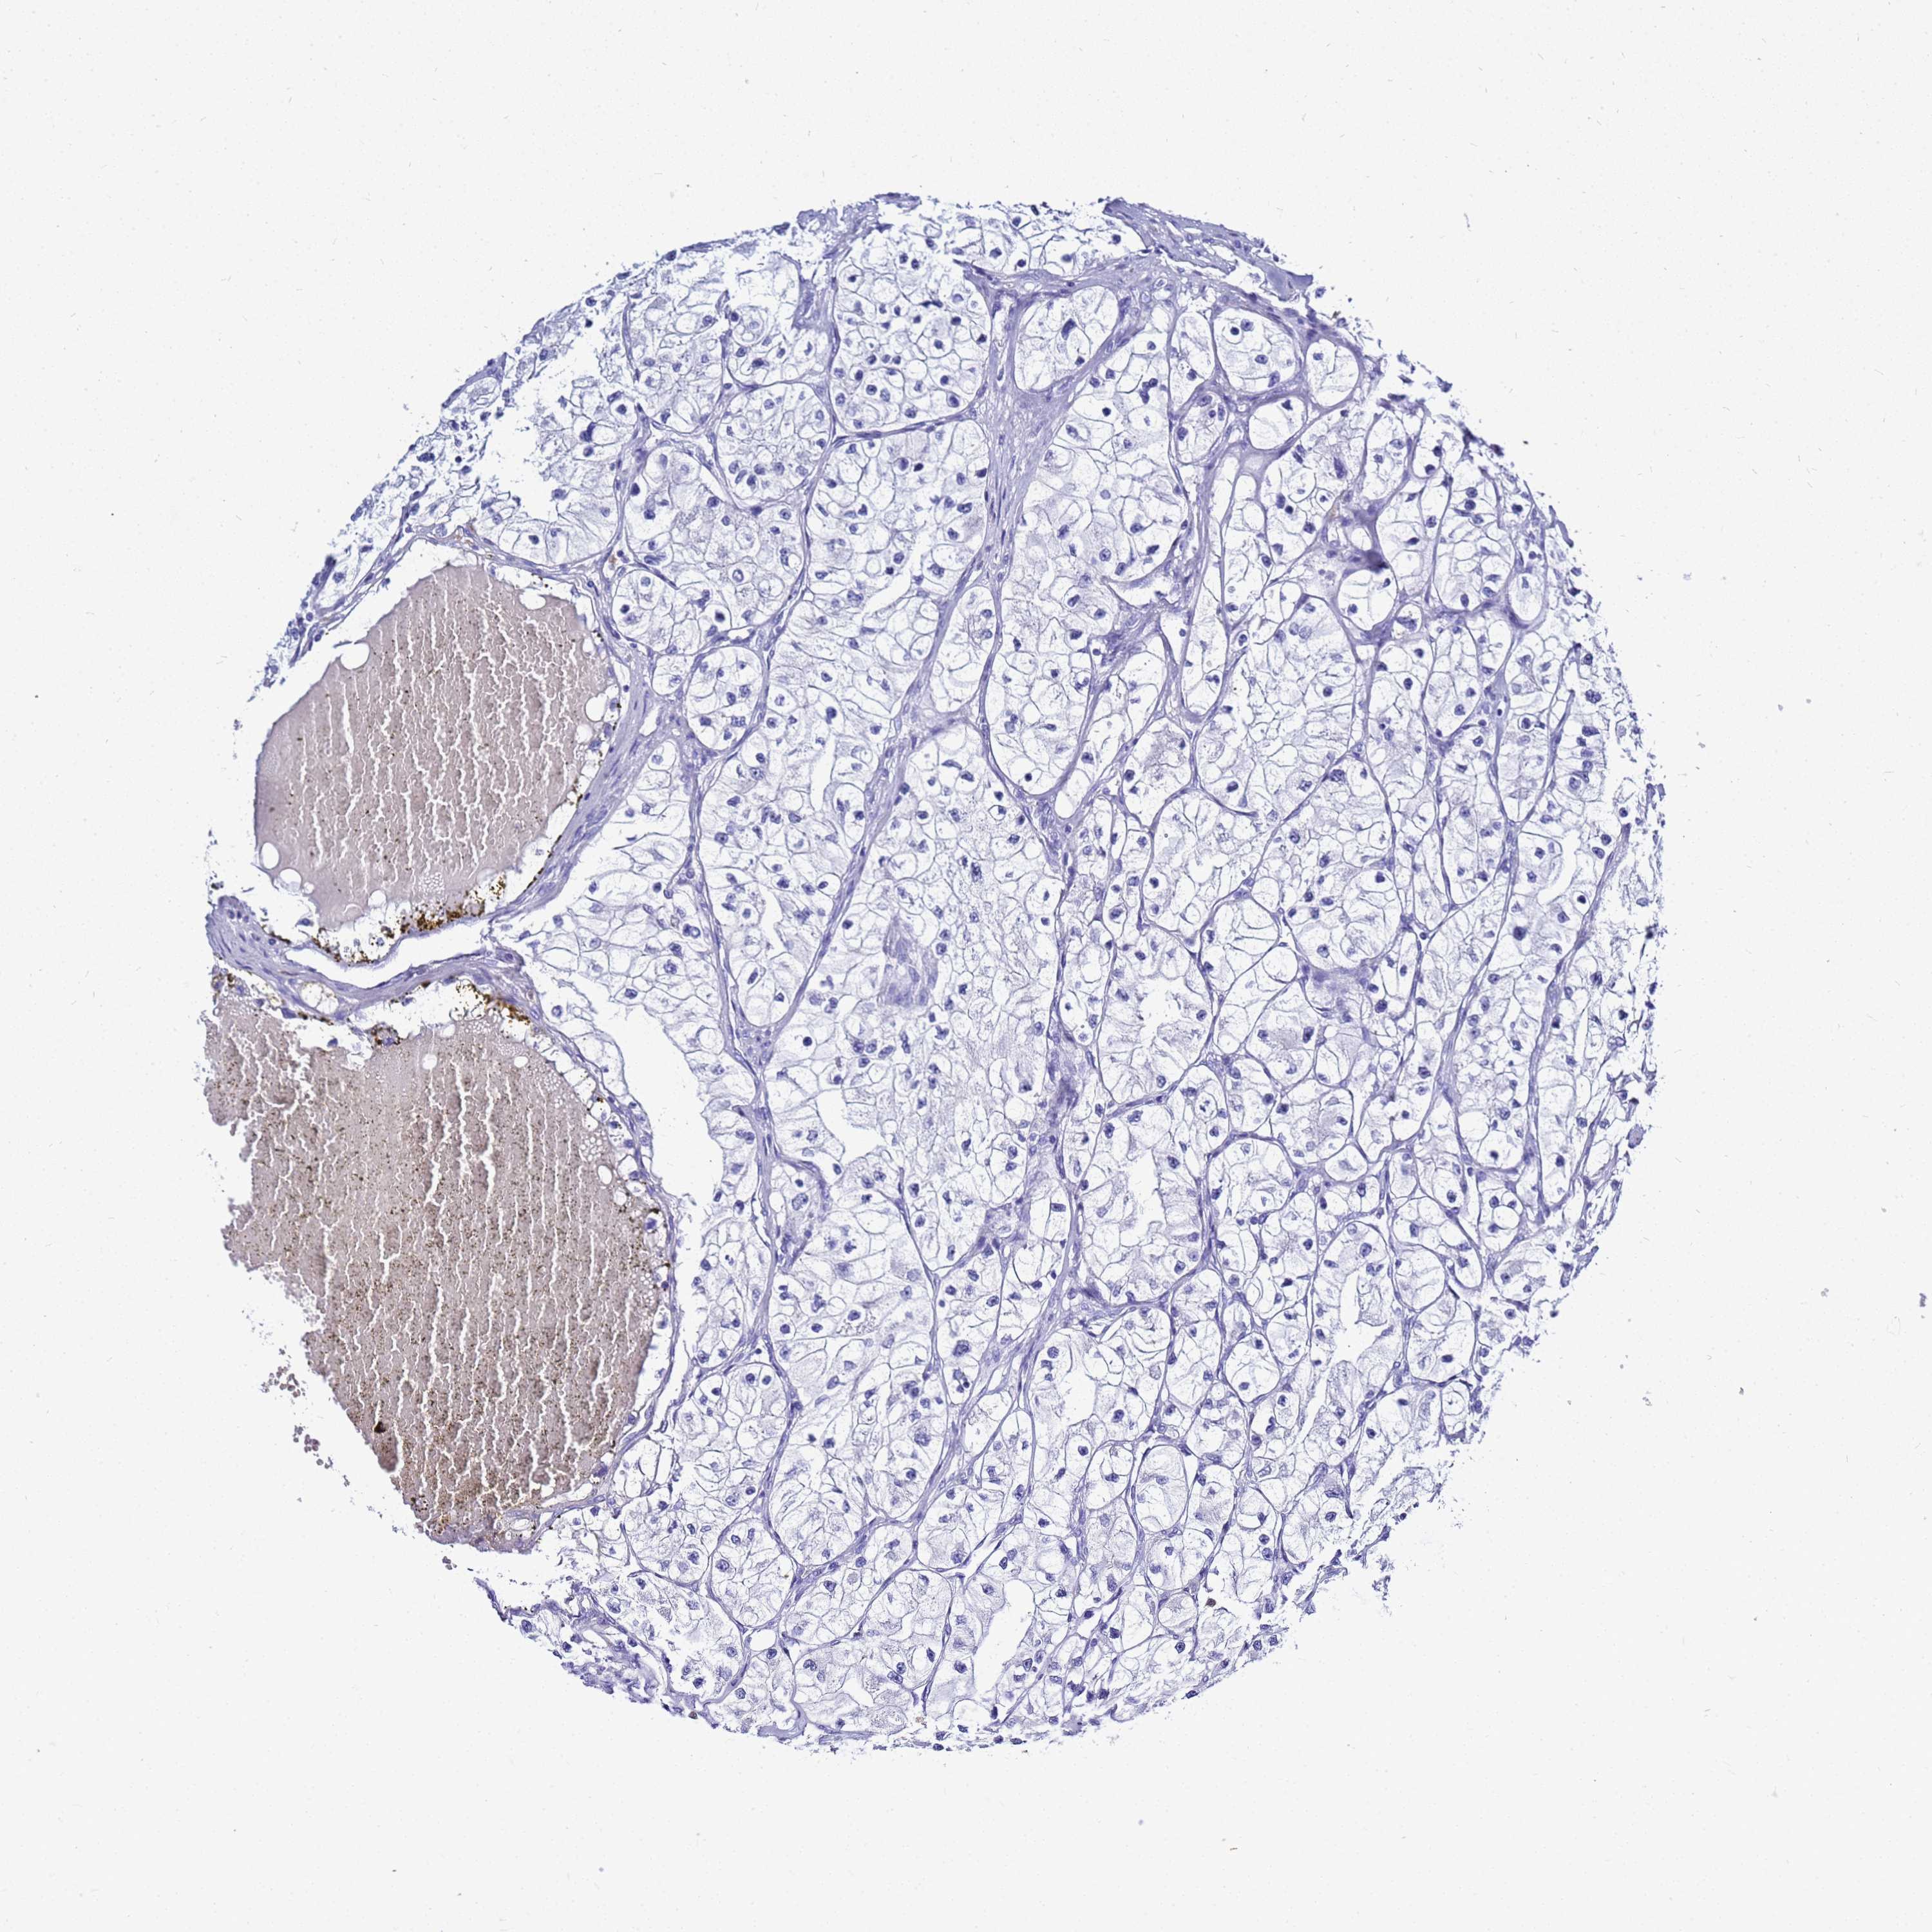

KIDNEY RENAL CLEAR CELL CARCINOMA (VALIDATION) - Interactive survival scatter ploti

The Survival Scatter plot shows the clinical status (i.e. dead or alive) for all individuals in the patient cohort, based on the same data that underlies the corresponding Kaplan-Meier plots. Patients that are alive at last time for follow-up are shown in blue and patients who have died during the study are shown in red.

The x-axis shows the expression levels (FPKM) of the investigated gene in the tumor tissue at the time of diagnosis. The y-axis shows the follow-up time after diagnosis (years). Both axes are complimented with kernel density curves demonstrating the data density over the axes. The top density plot shows the expression levels (FPKM) distribution among dead (red) and alive patients (blue). The right density plot shows the data density of the survived years of dead patients with high and low expression levels respectively, stratified using the cutoff indicated by the vertical dashed line through the Survival Scatter plot. This cutoff is automatically defined based on the FPKM cutoff that minimizes the p-score. The cutoff can be changed by dragging the vertical line or by entering a cutoff value in the square labeled "Current cut-off".

Under the Survival Scatter plot the p-score landscape (black curve; left axis) is shown together with dead median separation (red curve; right axis). Dead median separation is the difference in median mRNA expression between patients who have died with high and low expression, respectively. It is calculated as follows: median FPKM expression of dead patients with high expression - median FPKM expression of dead patients with low expression. This is intended to aid the user in visually exploring custom cutoffs and the associated p-scores and dead median separation.

Individual patient data is displayed and can be filtered by clicking on one or more of the category buttons on the top of the page. Categories describing expression level and patient information include: high, low, alive, dead, female, male and tumor stages. The scale of the x-axis can be toggled between linear and log-scale by clicking on the "x log" button. Mouse-over function shows TCGA ID, patient information and mRNA expression (FPKM) for each patient.

& Survival analysisi

Kaplan-Meier plots summarize results from analysis of correlation between mRNA expression level and patient survival. Patients were divided based on level of expression into one of the two groups "low" (under cut off) or "high" (over cut off). X-axis shows time for survival (years) and y-axis shows the probability of survival, where 1.0 corresponds to 100 percent.

CSTA is not prognostic in Kidney Renal Clear Cell Carcinoma (validation)

Best expression cut offi

Based on the FPKM value of each gene, patients were classified into two groups and association between prognosis (survival) and gene expression (FPKM) was examined. The best expression cut-off refers the FPKM value that yields maximal difference with regard to survival between the two groups at the lowest log-rank P-value. Best expression cut-off was selected based on survival analysis .

When clicking on this number, the vertical dashed line indicating cut-off, the interactive survival plot, and the Kaplan-Meier curve will be adjusted to show results based on the best expression cut-off.

: 19.04

P scorei

Log-rank P value for Kaplan-Meier plot showing results from analysis of correlation between mRNA expression level and patient survival.

N/A

TCGA RNA samplesi

RNA-seq data is reported as average FPKM (number Fragments Per Kilobase of exon per Million reads), generated by the The Cancer Genome Atlas (TCGA) .

Normal distribution across the dataset is visualized with box plots, shown as median and 25th and 75th percentiles. Points are displayed as outliers if they are above or below 1.5 times the interquartile range. FPKM values of the individual samples are presented next to the box plot.

Average pTPM 15.1

Number of samples 100